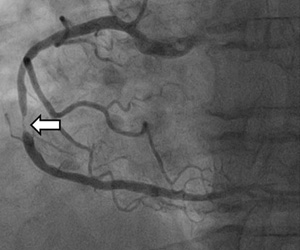

협심증은 심장에 혈액이 충분히 공급되지 못하여 가슴 통증이 발생하는 질환을 의미합니다. 협심증의 원인은 주로 심장의 동맥인 관상동맥이 좁아지거나 막히기 때문입니다. 관상동맥은 심장에 혈액을 공급하는 동맥으로, 이 동맥이 좁아지거나 막히면 심장에 충분한 혈액이 공급되지 못하여 가슴 통증이 발생합니다.

동맥경화: 동맥경화는 동맥 내부에 콜레스테롤, 지방, 혈전 등이 쌓여 동맥이 좁아지는 질환입니다. 동맥경화는 협심증의 가장 흔한 원인입니다.